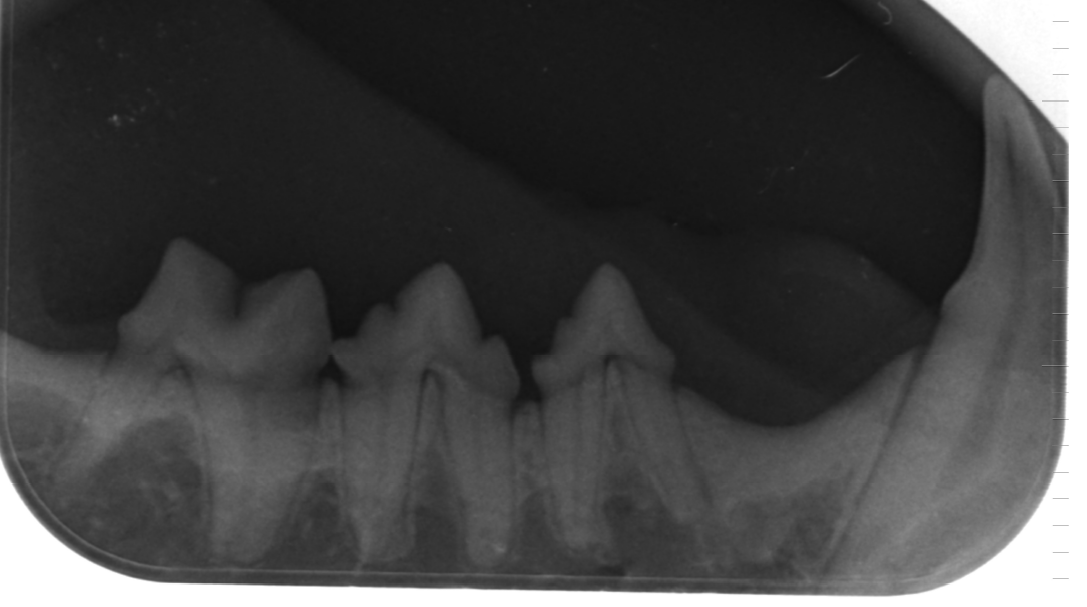

HD / ED / Digital X-ray

The x-rays are created digitally with a lot of experience.

Of course, a modern high-performance X-ray system with corresponding fully automatic development unit is in use.

Since 2001, we have been equipped with a digital X-ray unit for all cases of doubt, which enables particularly fine pictures with high transparency. These X-ray images are significantly better in their informative value than normal X-rays and thus often save the preparation of a computed tomography (CT). Conventional X-rays can also be taken by digitization in the data processing. In this form you can send them by e-mail. Since 2019 we do also offer x-rays with a digital Tooth X-Ray. This facilitates and accelerates the collaboration with consulting colleagues as well as the transmission of information during referrals, even over long distances.

Digital dental X-ray.